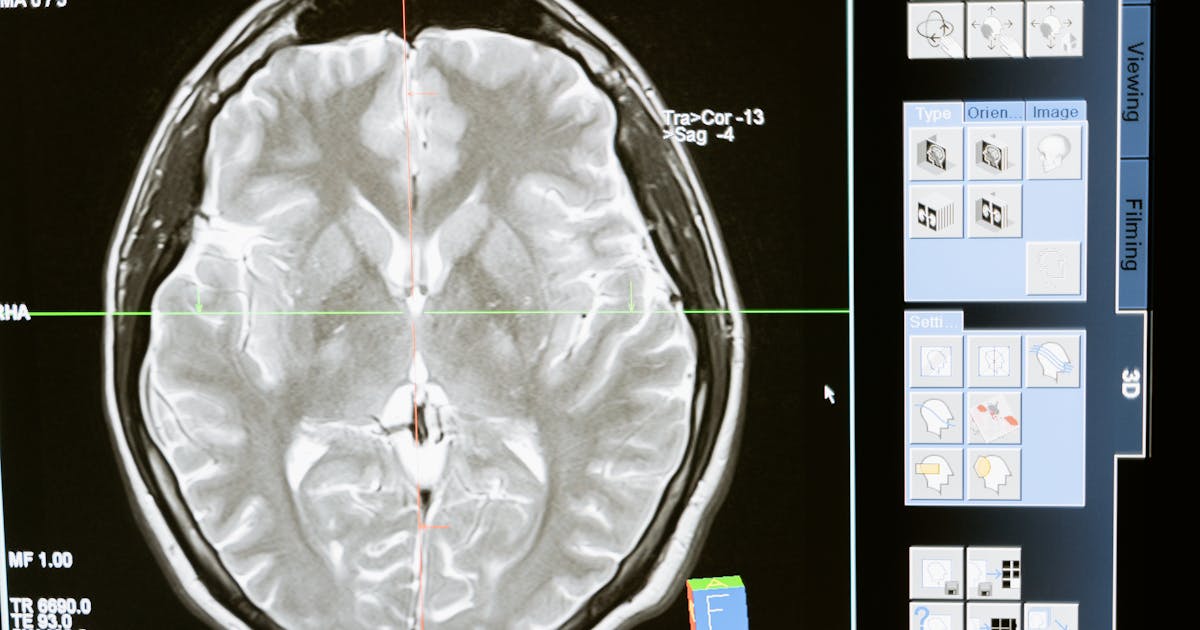

ヘルスケア / AI

ヘルスケア / AI

ヘルスケア / AI

医療機器メーカー向けAI画像診断支援システム

既存のPACSシステムとDICOM連携するAI胸部X線異常検出システムを開発。臨床グレードの精度を達成し、PMDA規制承認を取得しました。

35%

レビュー時間削減

94%

検出感度

10ヶ月

開発からPMDA承認